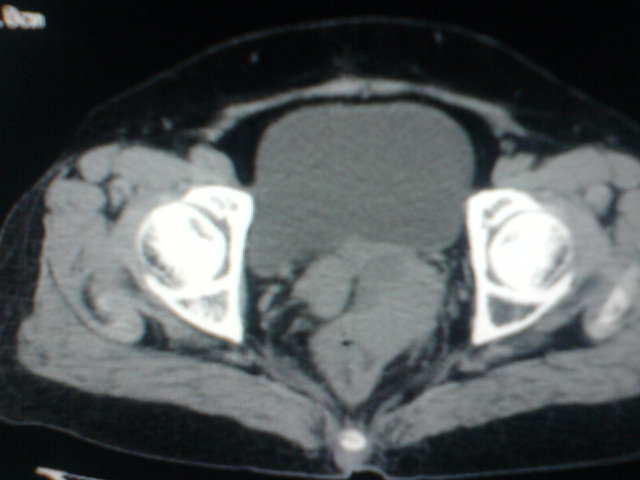

患者为老年女性,肿块最大层面不是位于宫颈,但宫颈偏后方有一囊状低密度影,肿块主要位于乙状结肠及直肠,所以考虑乙状结肠及直肠癌浸犯宫颈可能性大。

患者女性60岁 病史不详

宫颈癌侵犯直肠可能

考虑子宫内膜癌浸犯直肠。

考虑直肠癌侵及宫颈可能;建议增强扫描。

支持考虑宫颈癌上下前后通吃

考虑:直肠及乙状结肠癌侵及宫颈,囊性转移(假性粘液瘤)

支持宫颈癌侵犯直肠。

考虑直肠及乙状结肠癌侵犯邻近结构。